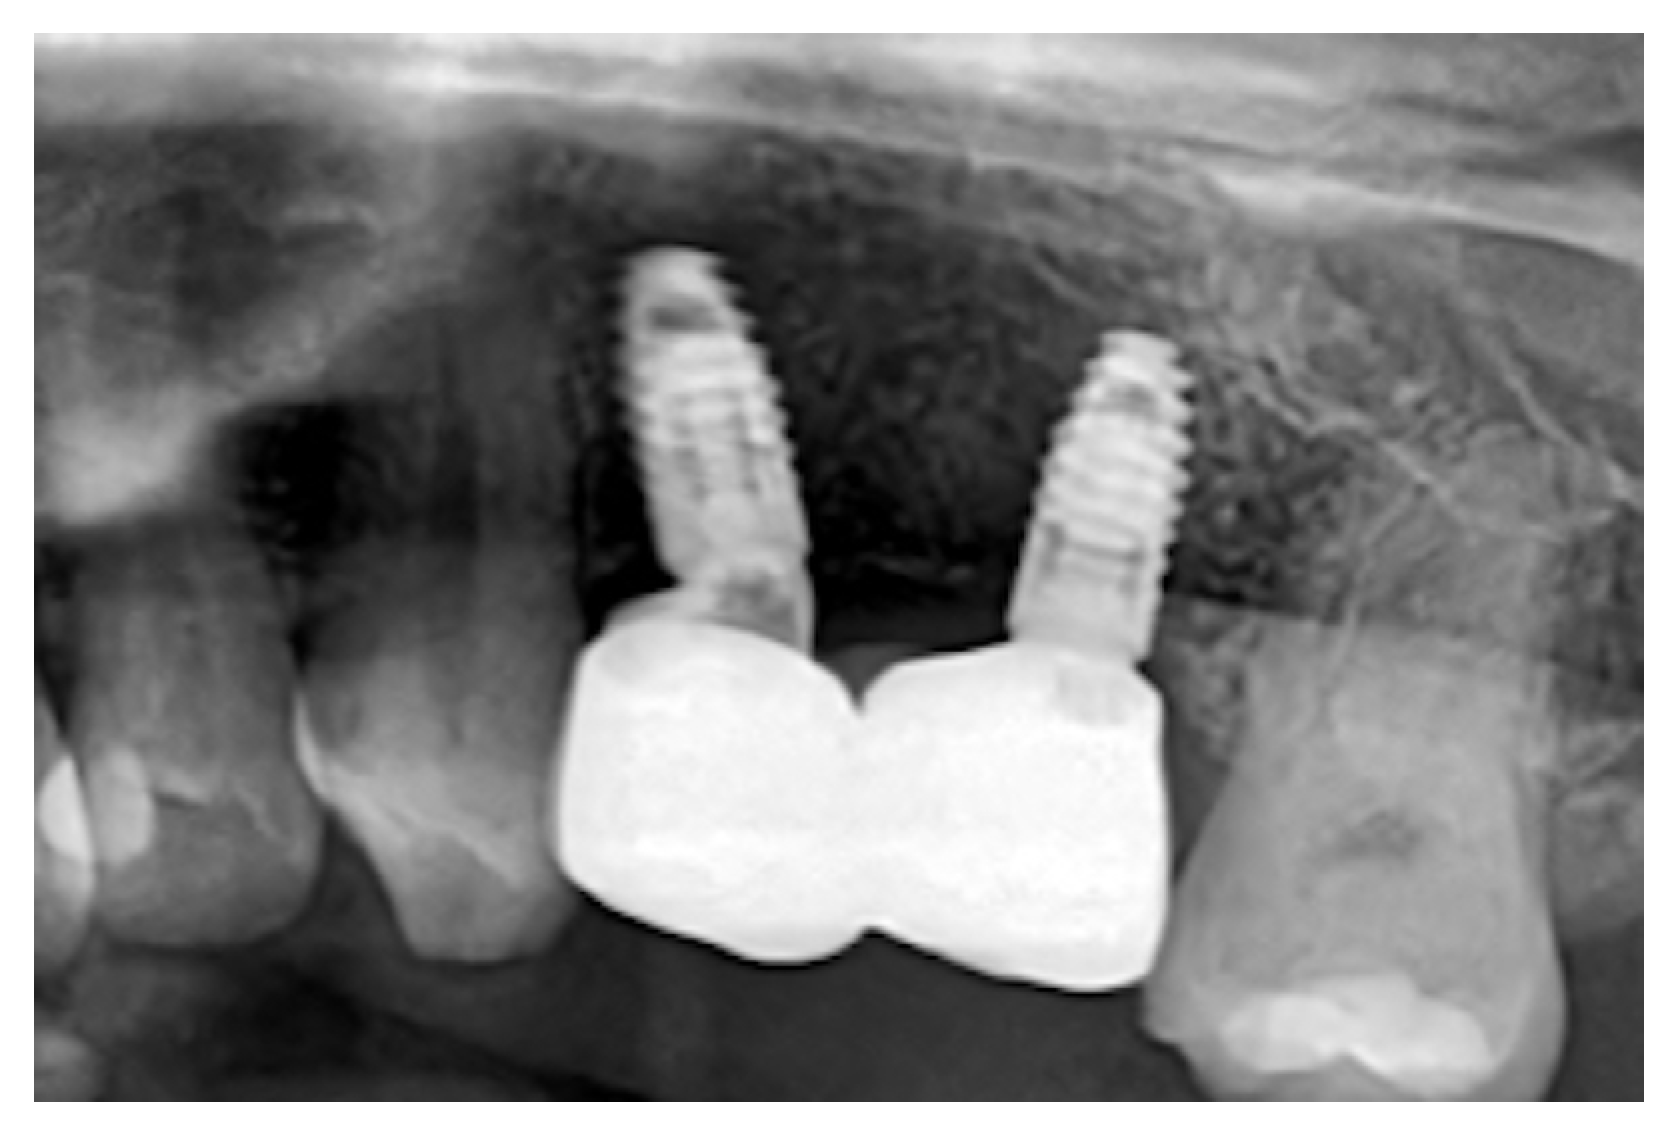

The vertical incision was then closed with simple interrupted sutures. (Figure 2B) Six months after the surgery, a CBCT scan was performed. Digital planning was performed using implant software, and two implants (BLT 3.3 mm × 8 mm, Straumann) were placed with insertion torques of 40 N·cm and 45 N·cm, respectively (Figure 2C). A zirconia fixed partial denture was screwed after two months (Figure 2D). After three years, an X-ray was performed(Figure 3). Upon palpation and probing, the periodontal tissues were healthy and showed no signs of inflammation.

Figure 3. Rx at the 3-year follow-up showing stable bone integration of the implants and preservation of marginal bone levels.